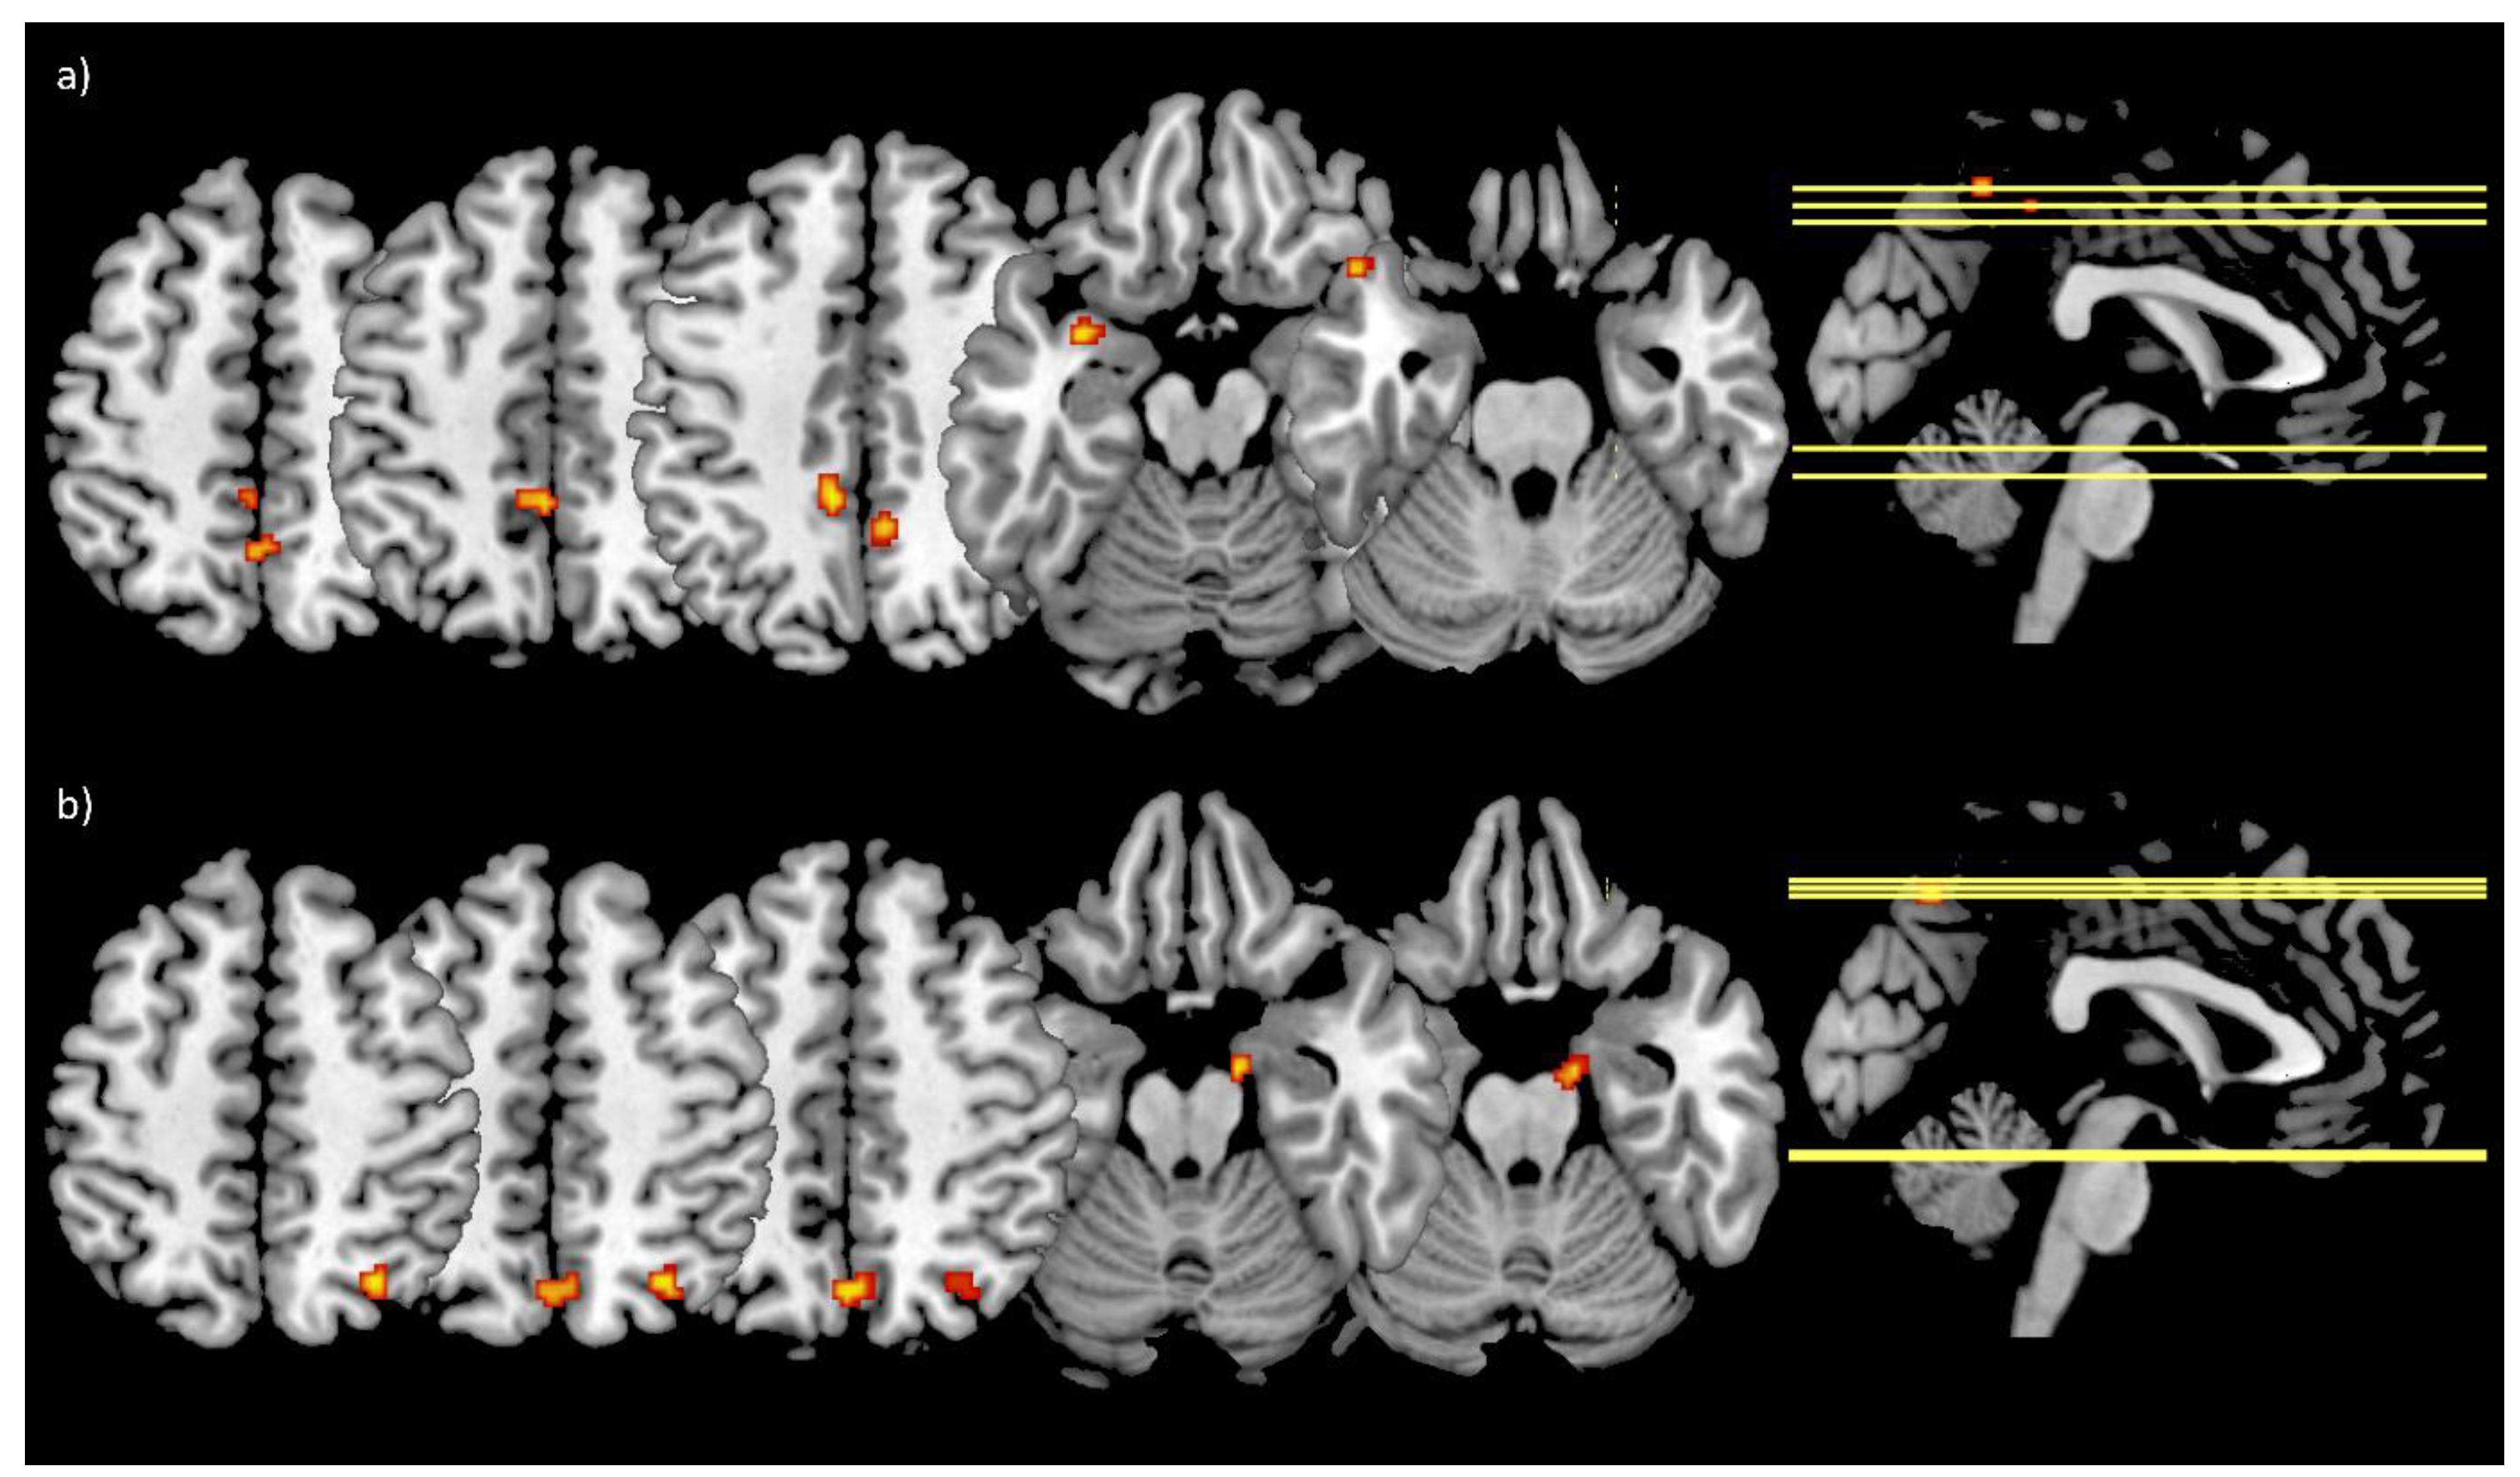

FC analyses revealed no significant main effects (time, group, or time by group interaction) for the bilateral amygdala seed. To search for trends the threshold exploratively was set to p < 0.001 uncorrected with a cluster size threshold of k ≥ 10 voxels. With the lower threshold, the time by group interaction showed an effect in the left middle cingulate cortex (peak voxel: [−8 −40 44]; k = 47), the precuneus (peak voxels: [6 −48 44], k = 16 and [0 −54 52], k = 13), and the left temporal pole (peak voxels: [−32 4 −16], k = 19 and [−48 20 −26], k = 12) (Figure 3a). Furthermore, the effect of time revealed an effect in the precuneus (peak voxel: [0 −68 50], k = 23), the right superior parietal lobule (peak voxel: [30 −64 52], k = 21), and the right parahippocampal gyrus (peak voxel: [14 −8 −20], k = 11) (Figure 3b).

Figure 3.

Main effects of the LME model for the bilateral amygdala FC changes. (a) Showing the clusters (red-yellow) derived from the time by group interaction within the left middle cingulate cortex, the precuneus, and the left temporal pole; (b) shows the clusters (red-yellow) from the main effect of time within the precuneus, the right superior parietal lobule, and the right parahippocampal gyrus; threshold: p < 0.001 uncorrected, k ≥ 10 voxels; IG: N = 18 (N = 16 at T6), CG: N = 10.